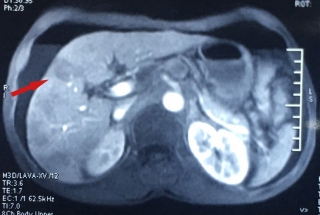

Các bác sĩ Khoa Ngoại Đầu Cổ - Bệnh viện Ung Bướu Hà Nội vừa phẫu thuật thành công cho cô giáo có khối u trong miệng khá hiếm gặp. Bệnh nhân được chẩn đoán trước mổ là u hỗn hợp tuyến nước bọt phụ chưa loại trừ ung thư. Khối u sinh mạch máu nhiều, nhẵn, to như quả táo, kích thước 3x3.5cm, ngay sát chân răng số tám bên phải, không di động. Kết quả chụp CT cho thấy khối u đã ăn mòn xương khẩu cái cứng, lan một phần vào sàn mũi.